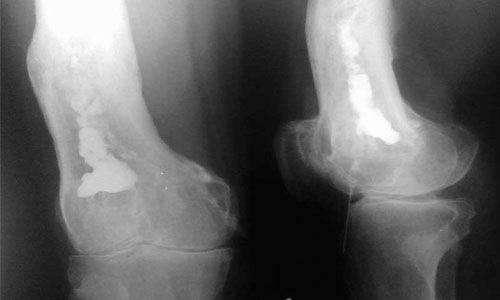

Рентгенография является подспорьем только после двух недель болезни. В зоне воспаления просматривается разрежение ткани, нечеткость костных контуров. Характерен линейный периостит – нечеткая тень, параллельная поверхности кости. Затем начинается некроз костной ткани с образованием секвестров.

Постепенно на снимках становится очевидным склерозирование, остеопороз и проявления периостита. Это говорит об уменьшении остроты и хронизации процесса.